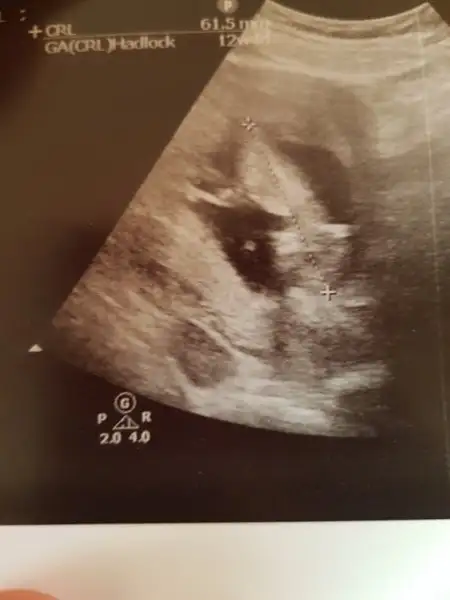

Bu da bizim mercimek :) İçerde dört dönüyor yaramaz :emir_bebek:

20171225_102341.webp